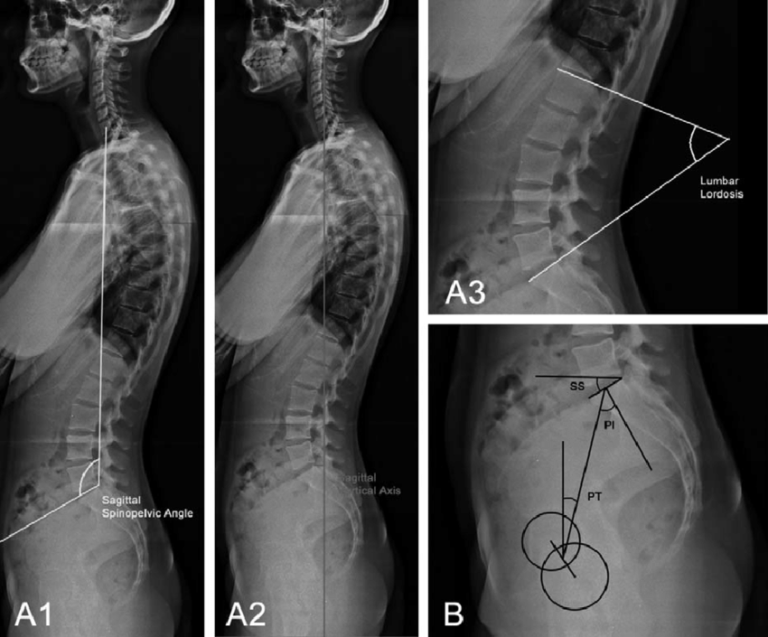

Es un estudio de radiografía de cuerpo entero que capta la columna vertebral completa, desde el cuello hasta el sacro, en una sola imagen. Se realiza de pie, permitiendo evaluar cómo se comporta la columna bajo carga.

🔹 Detección y monitoreo de escoliosis en niños y adultos.

🔹 Evaluación de desviaciones posturales como hiperlordosis o hipercifosis.

🔹 Diagnóstico de enfermedades degenerativas (artrosis, hernias discales).

🔹 Valoración postoperatoria en cirugías de columna.

🔹 Estudio de fracturas vertebrales y deformidades congénitas.